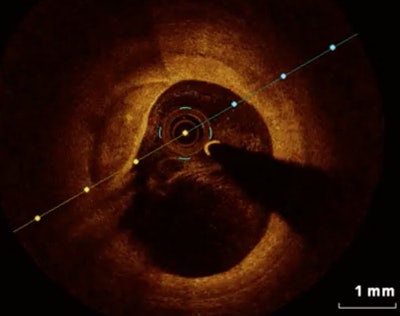

Thin-cap fibroatheroma at optical coherence tomography. Image courtesy of Dr. Mario Iannaccone.The prevalence of both coronary plaque rupture and thin-cap fibroatheroma was high, at more than 48% of this population for both manifestations, the authors reported. Thin-cap fibroatheroma seems to be a strong predictor of coronary plaque rupture in all acute coronary syndrome scenarios, they wrote (European Heart Journal -- Cardiovascular Imaging, 27 October 2015).

OCT has emerged in recent years as the most accurate modality for intracoronary evaluation, the authors wrote. It does an excellent job in characterization of plaque and is more accurate than intravascular ultrasound.